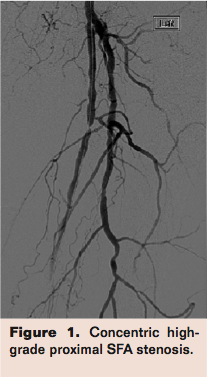

CLI patients tend to have severely calcified arteries, posing a challenge to both surgical and endovascular revascularization techniques. Surgical bypass is feasible in ambulatory patients with a reasonable surgical risk, long occlusions, a patent IP artery that provides direct flow to the foot, and an adequate autologous venous conduit. The candidacy of CLI patients for bypass is often compromised by poor or inadequate length of autologous vein, poor skin nutrition, significant medical comorbidities and calcified, diseased targets. From the endovascular standpoint, one of the most common challenges is the severely calcified lesion that is not dilatable by balloon angioplasty, leading to an unresolved high-grade stenosis (Figures 1-3). These resistant, recalcitrant lesions are also associated with spiral dissections and perforations and can present a physical barrier for the penetration of the antiproliferative drugs delivered by current drug-eluting stents and balloons. They have also been recognized as one of the predisposing factors that lead (in conjunction with forces of contraction, extension, torsion, compression, and flexion) to stent fractures (Figure 4).